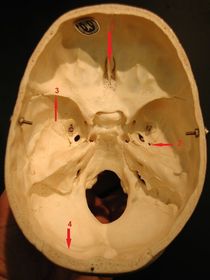

1) identify 1 2) structure passing through 2 3) structure attached 4) structure related 1) crista galli 2) middle meningeal artery and nernous spinosus 3) attached margin of tentorium cerebilli 4) left transverse sinus